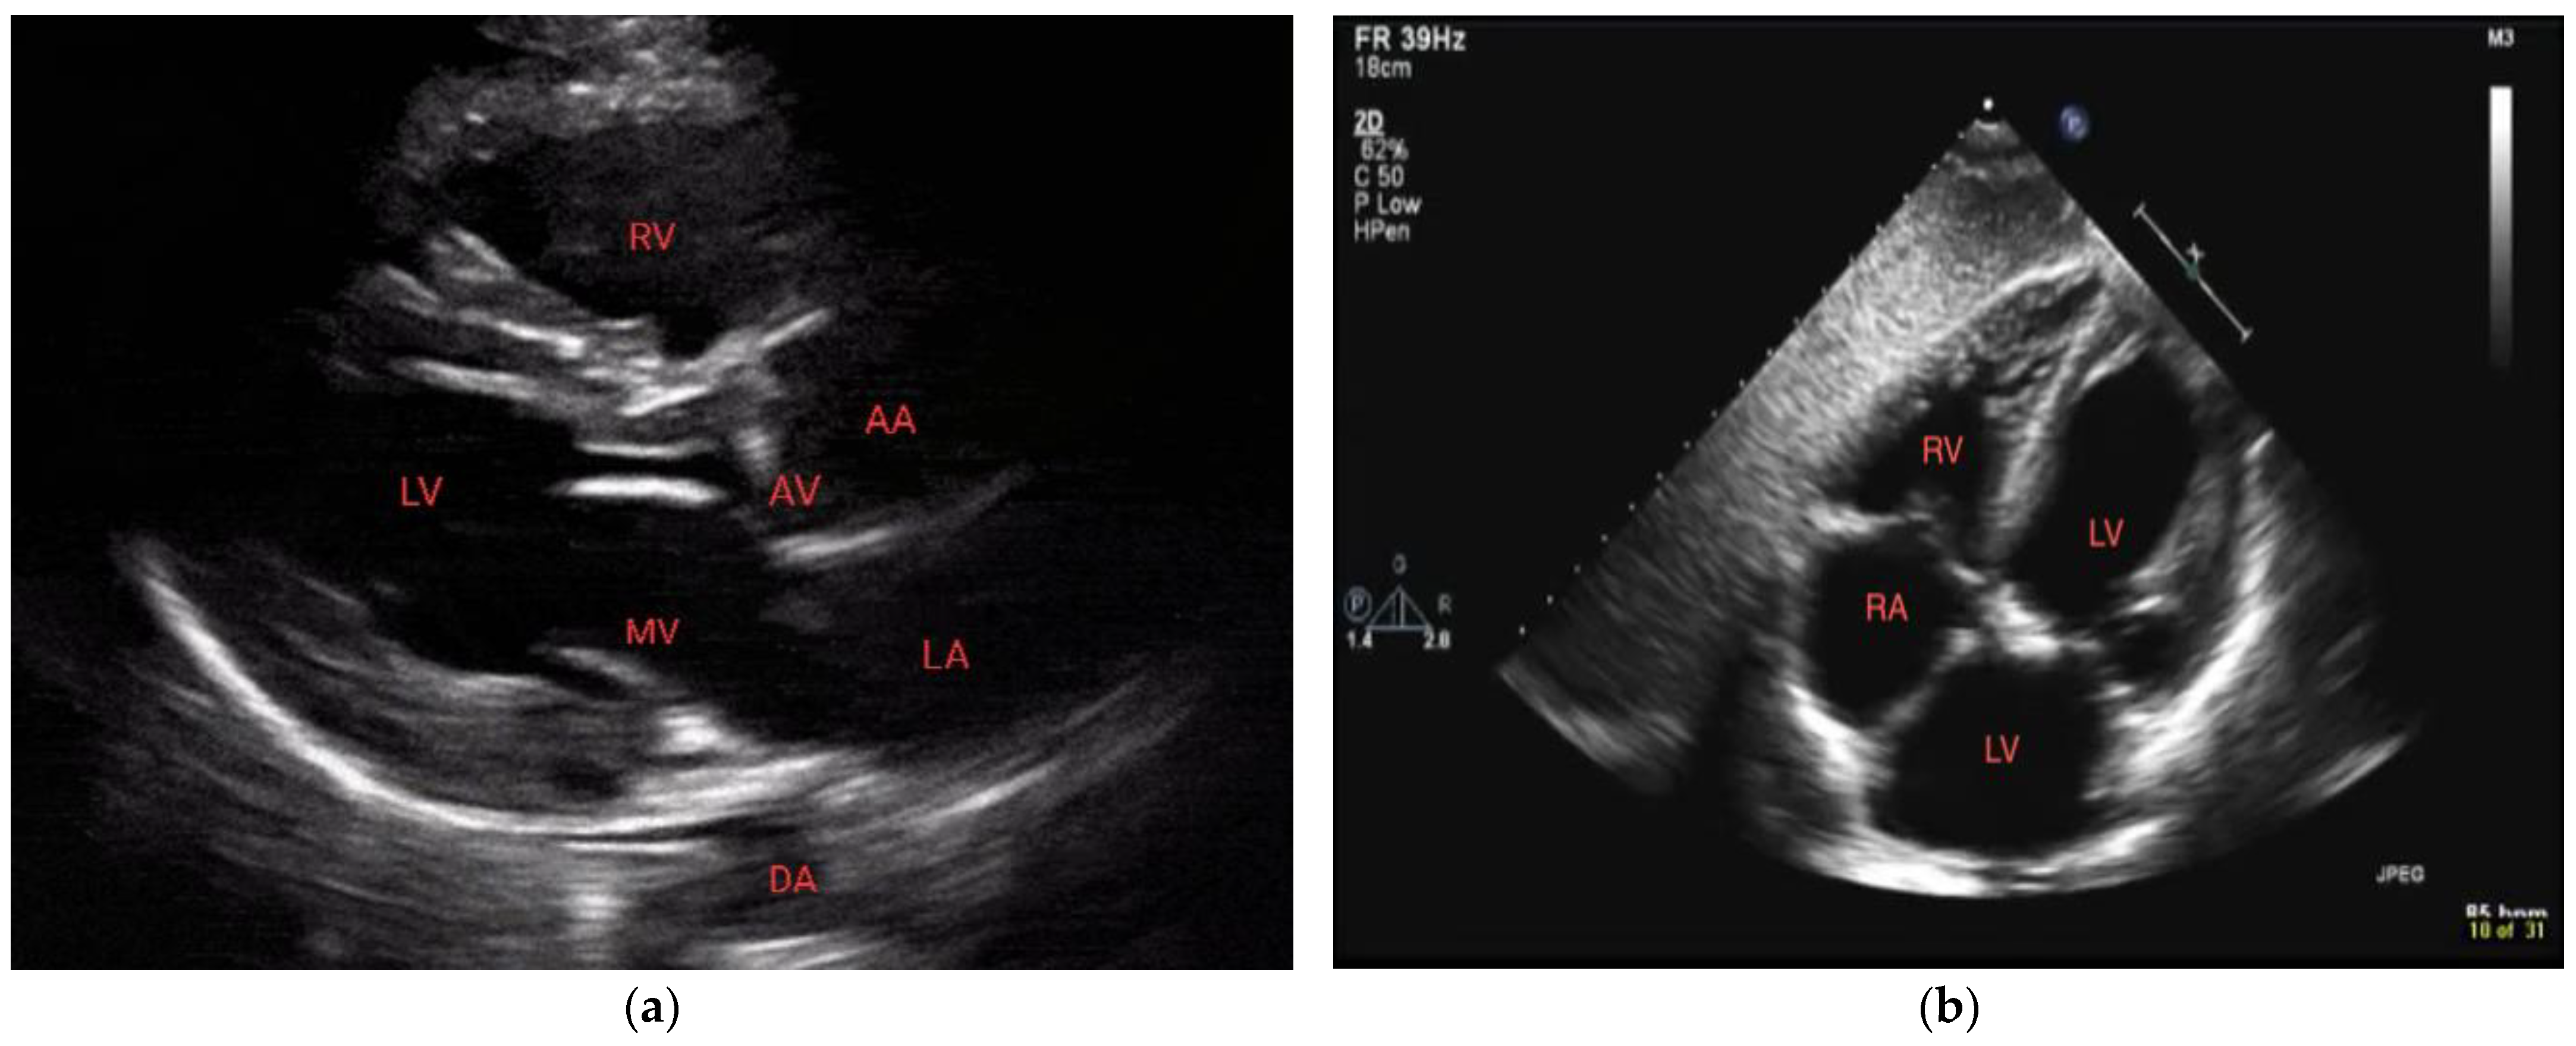

POCUS can be focused on a cardiac view or it can include other windows. In performing POCUS during cardiac arrest, the ideal probe is dependent on the goal. A phased array transducer, working at low frequencies (1–5 Hz) and providing high resolution, is usually adopted as the cardiac probe. A linear transducer (7–15 MHz) is optimal for the lung window and pneumothorax, thereby allowing via its high frequencies detailed imaging of the pleural line [7,8]. Deep tissue and abdomen evaluation is best carried out with a convex probe characterized by a wide footprint and frequencies ranging from 2.5 to 7.5 MHz. Regardless of the availability of different probe options, it is preferable to mostly rely on one probe, preferably a phased-array probe, during cardiac arrest scenarios. This is because the phased-array probe offers versatility and comprehensive assessment capabilities, thus allowing for efficient evaluation of both cardiac activity and lung function. The main difference between echography during cardiac arrest and standard echography lies in the approach and timing used. Rapid acquirement of a single view is the aim during the critical event of cardiac arrest where precious seconds cannot be spent evaluating multiple measurements and views as is the case with standard echography. With this objective in mind, the subxiphoid approach has traditionally been the preferred window as it can be performed during ongoing CPR. Nonetheless, the parasternal long-axis view demonstrated superiority compared to the subxiphoid view regarding the rapidity of execution as well as the quality of the cardiac image [9] (Figure 1). Ultimately, patient characteristics (e.g., body habitus), as well as the environment and the accessibility to the patient (particularly in a prehospital context), may dictate the best view for each situation [9,10].

Figure 1.

Normal parasternal long-axis view (a) and subxiphoid view (b). RV = right ventricle, LV = left ventricle, MV = mitral valve, DA = descending aorta, AA = ascending aorta, and AV = aortic valve.